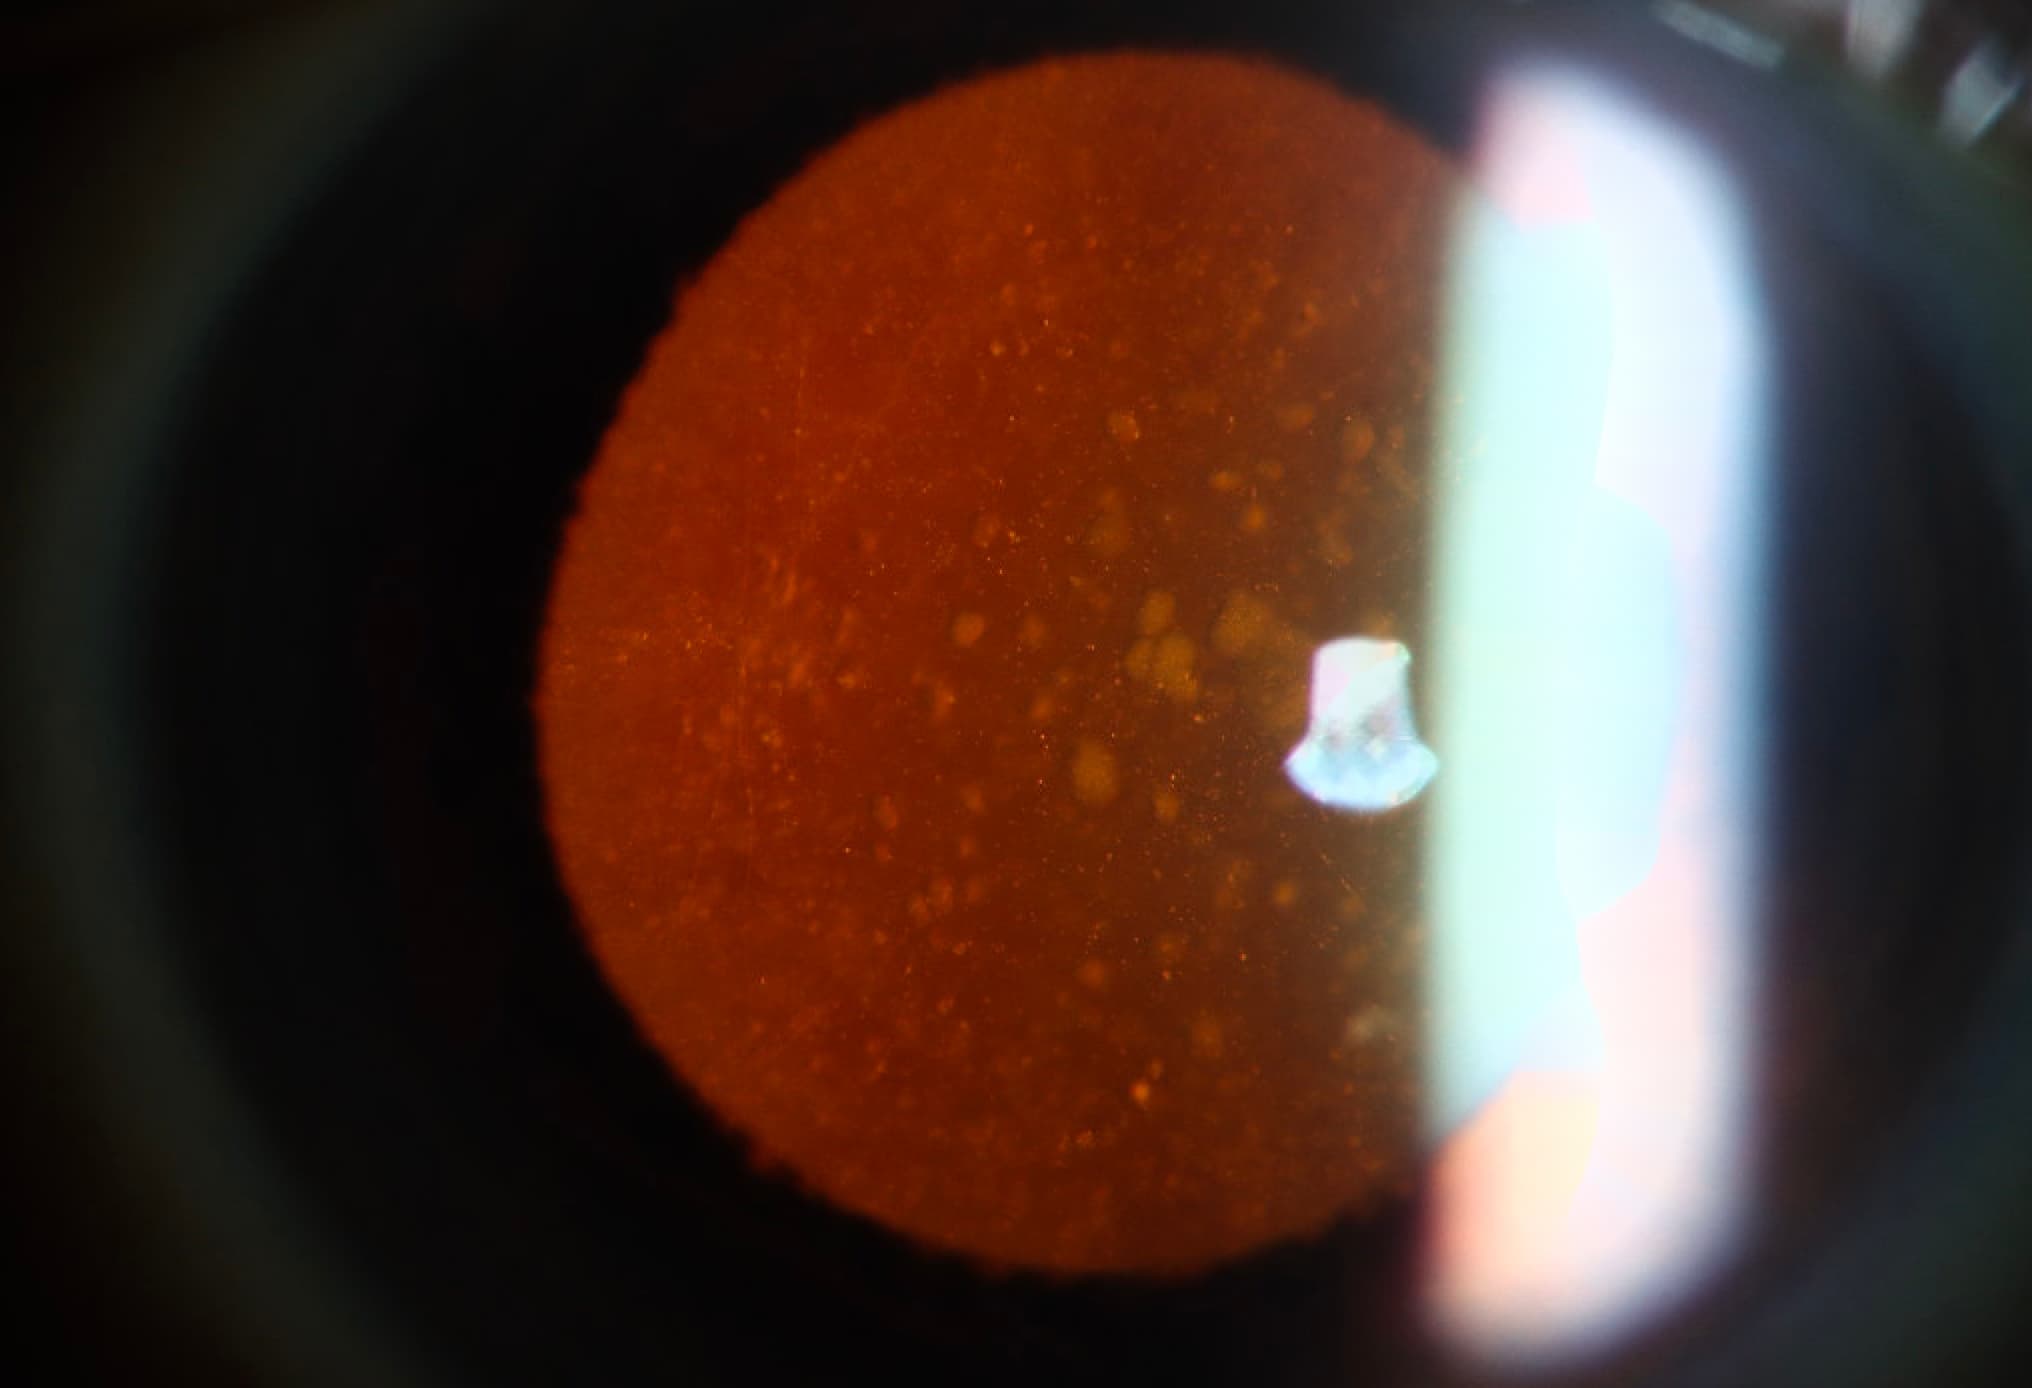

Clinical Images

High-resolution clinical photographs showing various presentations of glaucoma.